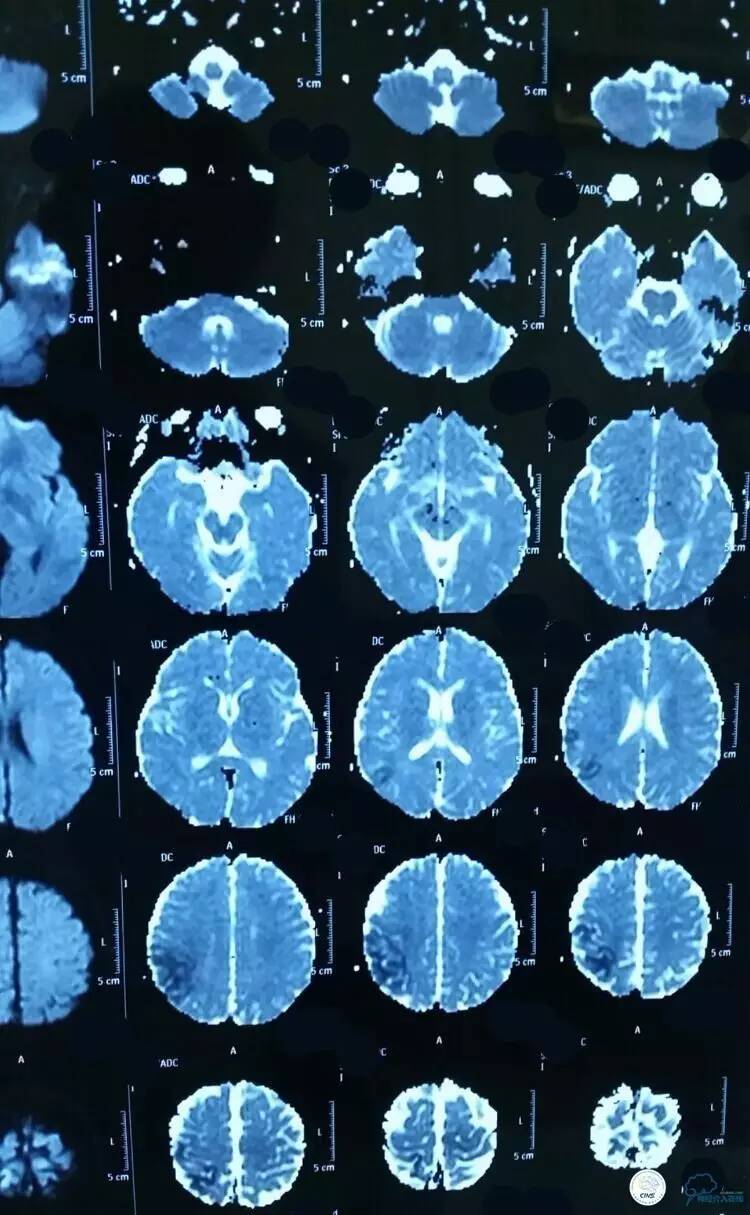

▼术前MRV提示上矢状窦完全闭塞,左侧横窦、乙状窦充盈不良。

▼术前MRV:

▼术前造影和MRV一致: